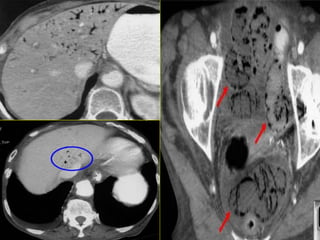

63-year-old woman status post aortic valve replacement who presents with a one

week history of abdominal pain becoming quite severe over the last 24 hours.

63-year-old woman statuspost aortic valve replacement who presents with a one week history of abdominal pain becoming quite severe over the last 24 hours.